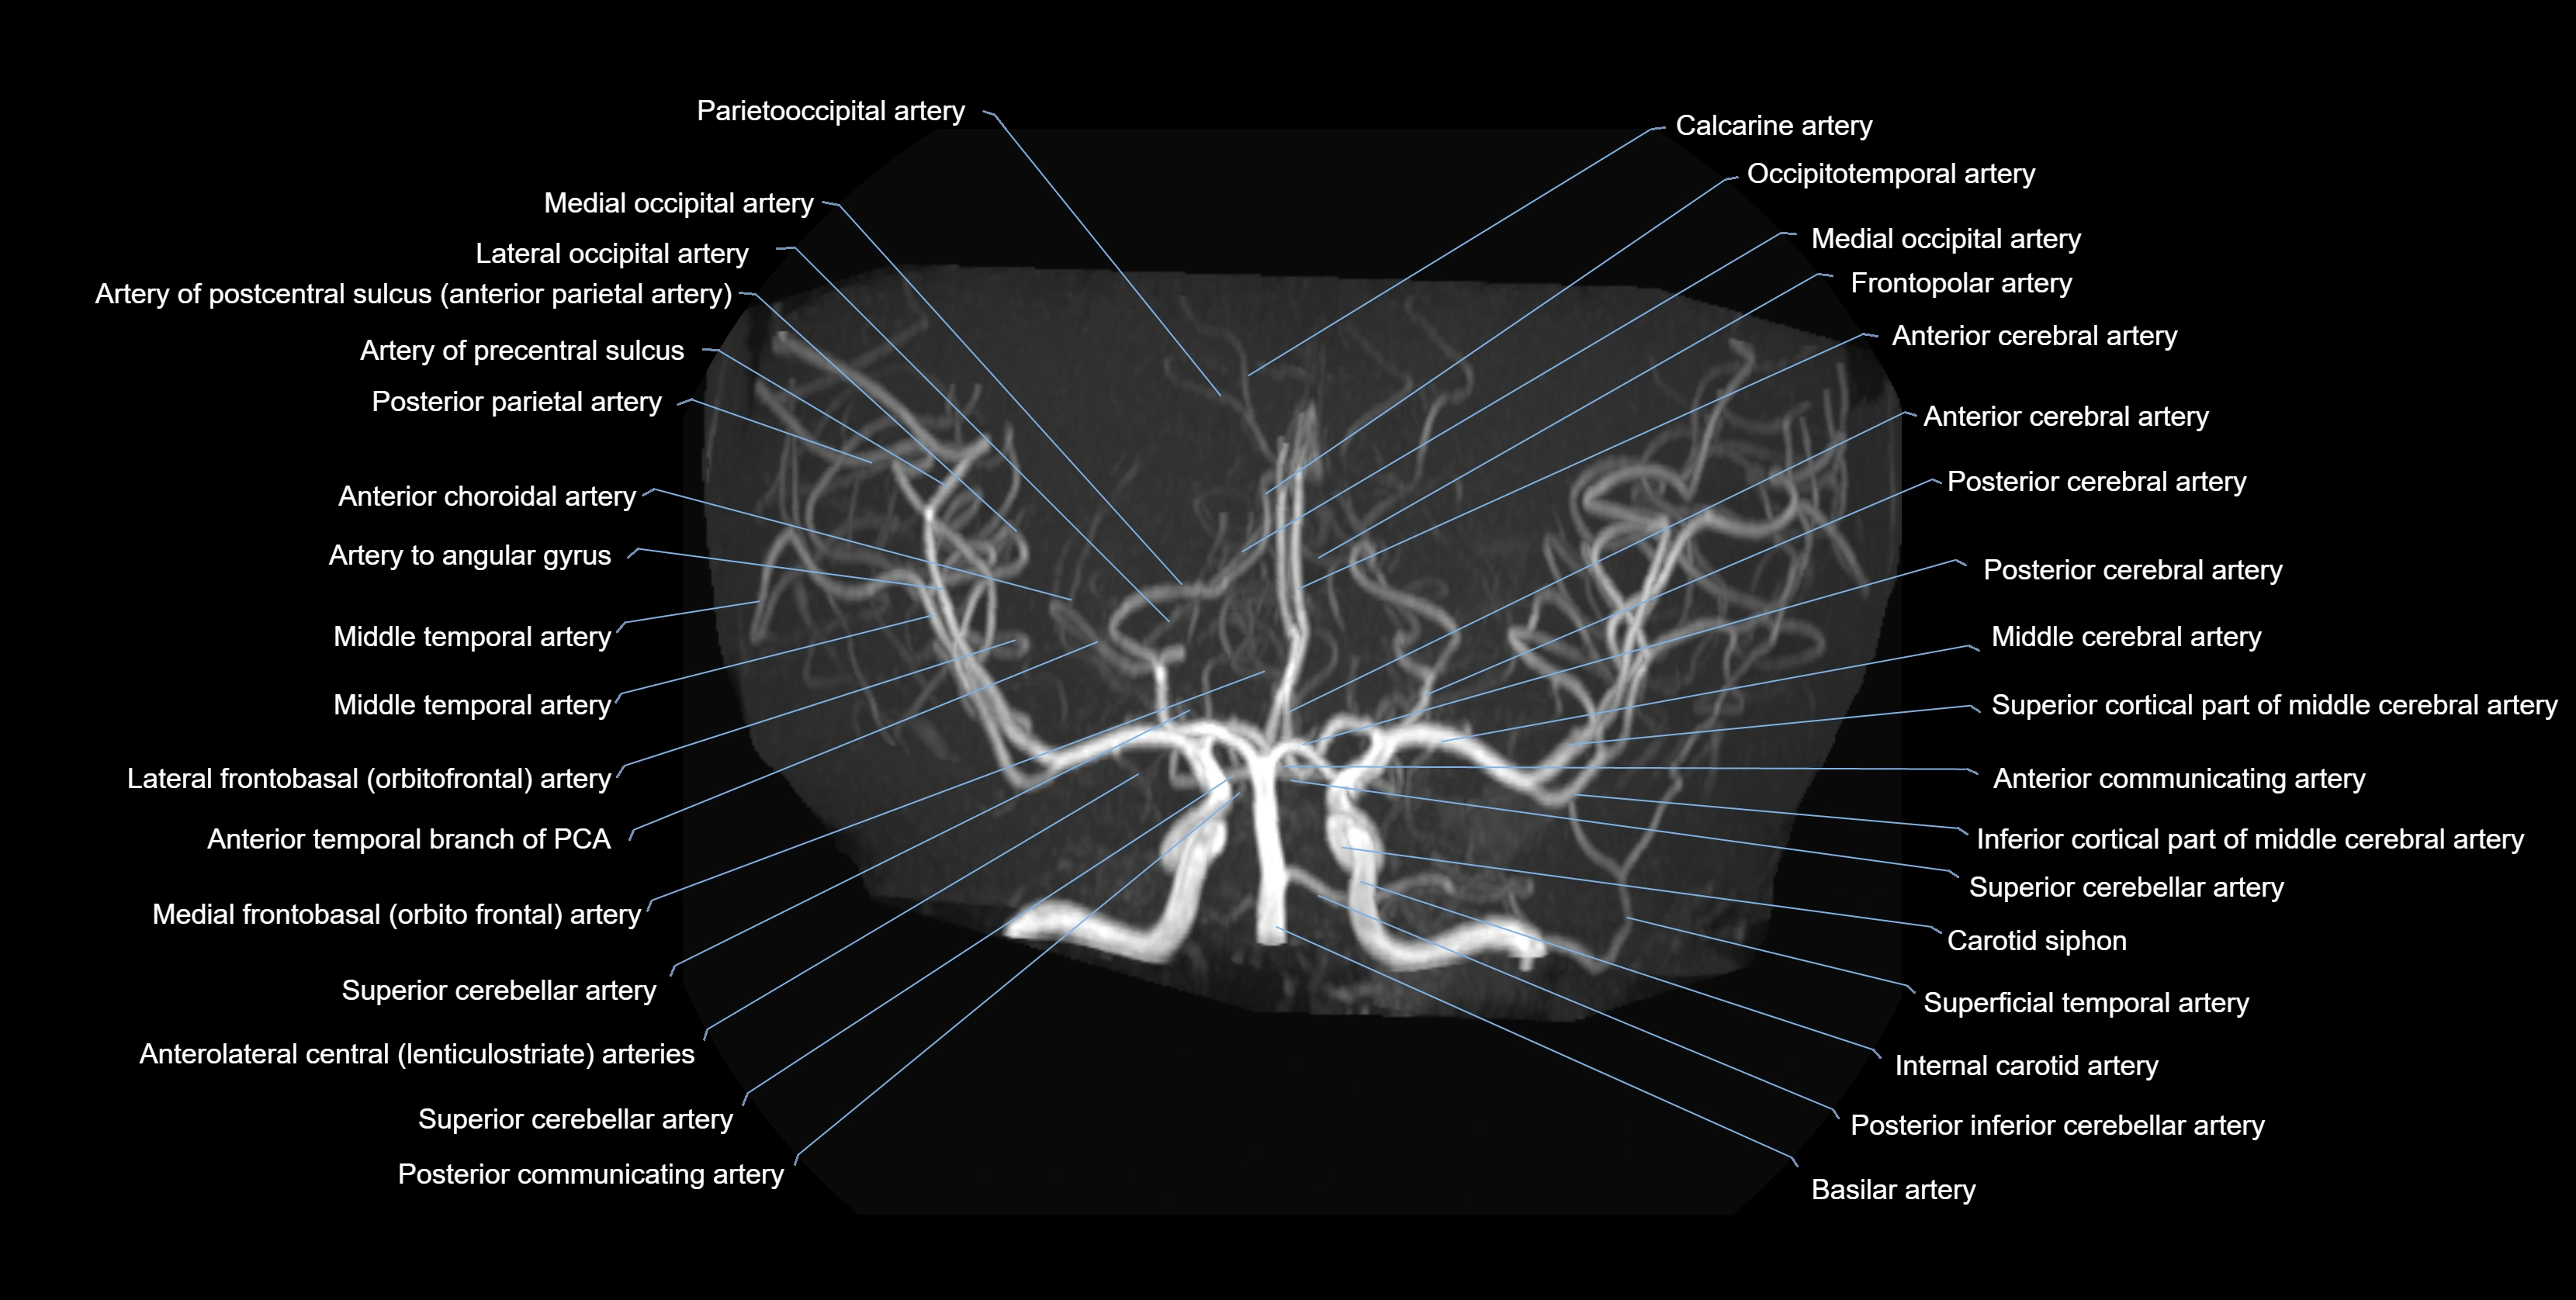

CTA (CT Angiography):

• Opacified with iodinated contrast, AChA appears as a bright high-attenuation vessel

• Visualized from ICA origin along optic tract toward choroid plexus

• 3D reconstructions depict its course and relation to adjacent arteries

• Gold standard for identifying aneurysms, occlusion, or vascular anomalies